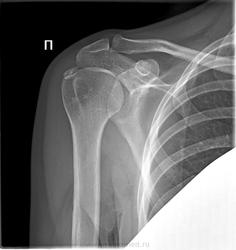

Рис. 2. Больная П., 45 лет. Диагноз: плечелопаточный периартрит. “Каменный” бурсит. В мягких тканях над большим бугорком плечевой головки определяется овальной формы кальцификат гомогенной костной плотности.

Вопрос... уместным ли будет в данном случае предположить возможность импиджмент-синдрома, учитывая наличие дополнительного образования костной плотности у большого бугорка?

Возможность есть. "Обычно, имеется достаточный промежуток между акромионом и вращательной манжетой, так что сухожилия при движениях в плечевом суставе свободно скользят под акромионом. Однако всякий раз, когда вы поднимаете руку, происходит небольшое сдавление сухожилий и суставной сумки между головкой плечевой кости и акромионом. Это явление носит название импинджмент."

Возможно не бурсит, а кальцинат в толще сухожилия. Надо УЗИ или МРТ провести.

Описал, как оссификацию сухожилия надостной мышцы. Может быть и последствием травмы, не только импинджмента.